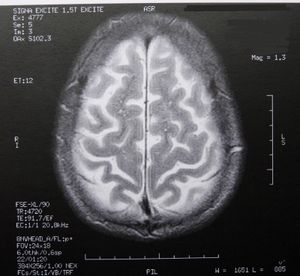

Gehirn: Scans verbessern die Diagnose erheblich (Foto: pixelio.de/Dieter Schütz) |

Zu Beginn der Studie wurde bei den Patienten ein Gehirn-Scan mittels fMRT durchgeführt. Die Analyse dieser Daten sollte zeigen, ob das Ergebnis der beiden Behandlungsansätze vom Zustand des Gehirns vor dem Behandlungsbeginn abhing. Die MRI-Scans haben ergeben, dass das Ausmaß der funktionellen Konnektivität zwischen einem wichtigen Zentrum zur Verarbeitung von Gefühlen, einem Teil des Gyrus cinguli und drei anderen Bereichen des Gehirns in einem Zusammenhang mit den Behandlungsergebnissen steht.

Patienten mit einer positiven Konnektivität zwischen den Gehirnregionen erreichten mittels Verhaltenstherapie viel eher eine Remission. Jene mit einer negativen oder fehlenden Konnektivität sprachen eher besser auf Antidepressiva an. Laut der leitenden Wissenschaftlerin Helen Mayberg erfordern Depressionen wie die verschiedenen Arten von Krebs auch eine unterschiedliche Behandlung. "Mithilfe dieser Scans könnten wir in der Lage sein, dem Patienten jene Behandlung zu geben, die am ehesten hilft."